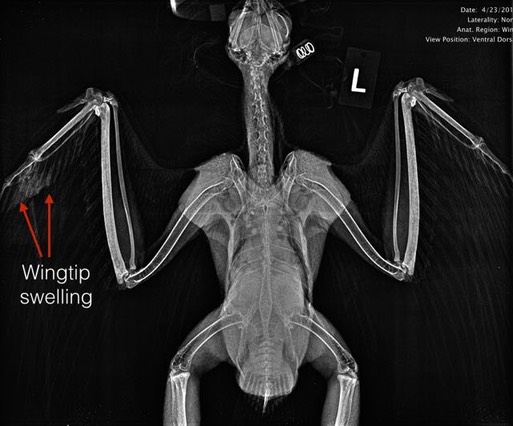

Joe and Cordi Atkinson found an injured Swainson’s Hawk at the base of a power pole on their ranch near Vale, OR. It was one of a pair who have nested on the ranch for a number of years. Tara was again called on to help transport the bird to Pendleton.

An exam revealed the hawk was in excellent physical condition, especially amazing considering she had just completed her spring migration from Argentina to eastern Oregon. We also found burns on both feet and a small wound and broken primary feather on her right wingtip, indicating she had been electrocuted.

A radiograph confirmed slight swelling in her right wingtip.